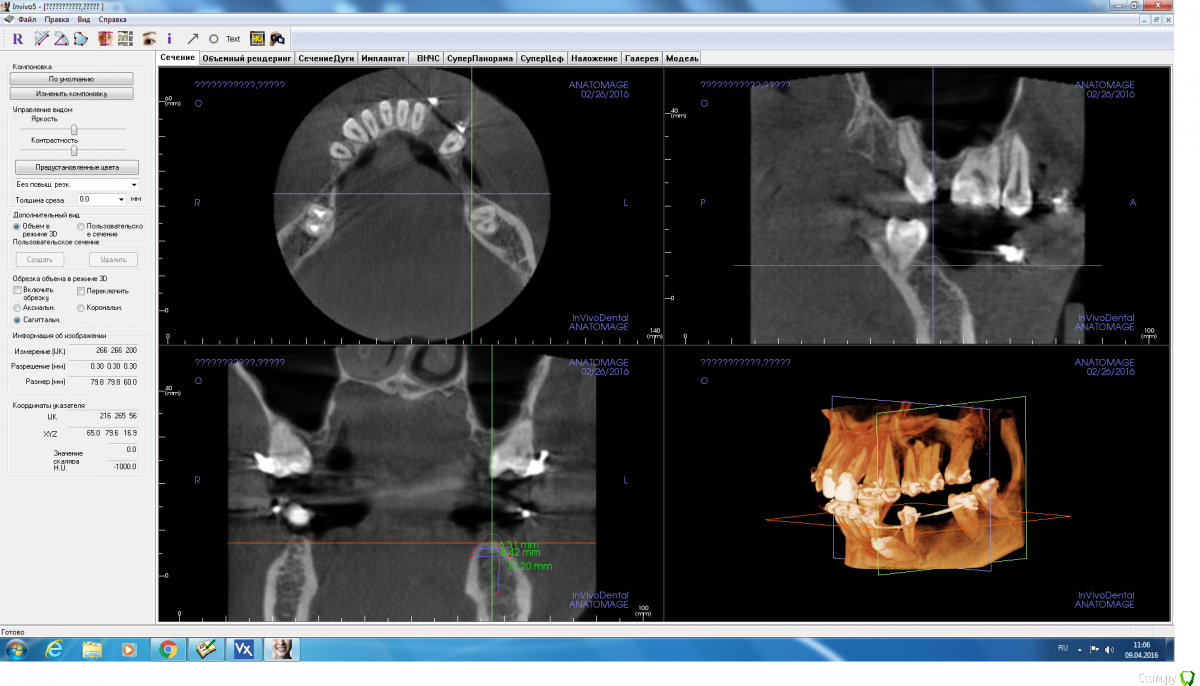

Fibez Опубликовано 8 апреля, 2016 Поделиться Опубликовано 8 апреля, 2016 Ред_бутлер, там же всего 10 мм от края гребня до канала? Куда заглубляться-то? Или ставить 3,5х8мм? Ссылка на комментарий

Aquarius Опубликовано 8 апреля, 2016 Поделиться Опубликовано 8 апреля, 2016 8,5 вполне себе рабочий размер Ссылка на комментарий

red_butler Опубликовано 8 апреля, 2016 Поделиться Опубликовано 8 апреля, 2016 Ред_бутлер, там же всего 10 мм от края гребня до канала? Куда заглубляться-то? Или ставить 3,5х8мм?С чего Вы взяли, конечно выставленные скрины полной информации не дают, но мне видятся 12-14 мм Ссылка на комментарий

adamskot Опубликовано 9 апреля, 2016 Автор Поделиться Опубликовано 9 апреля, 2016 Пойду на аутоблок, с ретромолярной области, чтобы восполнить потерю вестибулярно в позиции 35.В позиции 36 поставлю одновременнно через 4 мес с 35. Будет более бюджетно, нежели мембрана,ксено и скребок...Надеюсь, срезы сейчас удачны для обзора)) Ссылка на комментарий